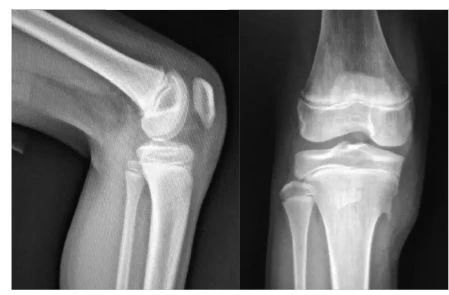

男,11岁,胫骨前结节稍肿胀,右膝疼痛两月余,按压疼痛,胫骨结节下部与骨干分离。

X线片可显示胫骨结节骨软骨炎患者骨质及软组织的异常改变,是诊断胫骨结节骨软骨炎颇有价值的方法,对一些早期及可疑患者可进一步做CT或MRI检査